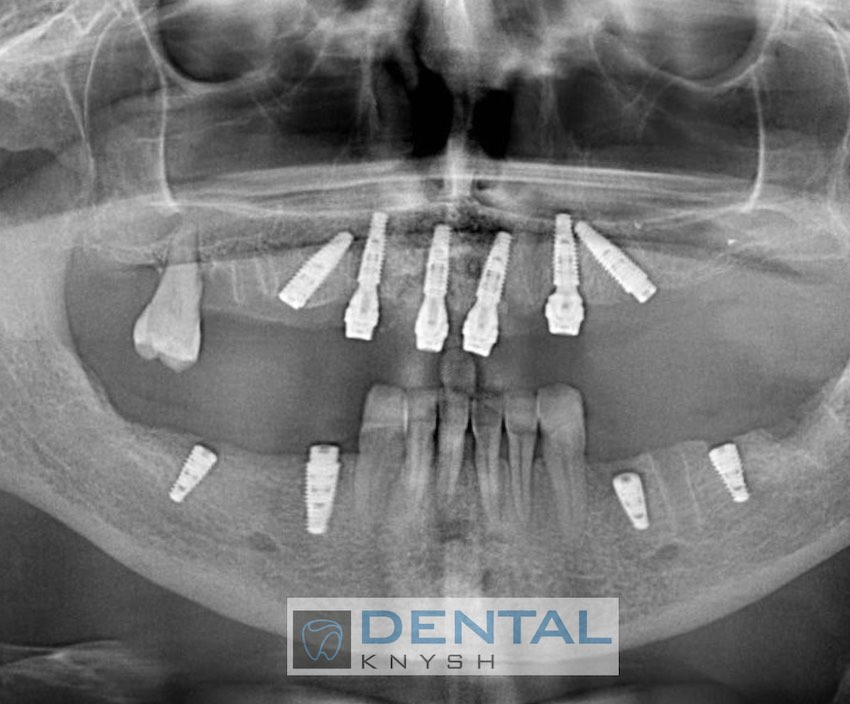

Сканы КТ имплантации зубов, 2026-04-18

Скан КТ, 2026-04-18

Сканы КТ имплантации зубов, 2026-04-18

Скан КТ имплантации зубов, 2026-04-17

Сканы КТ имплантации зубов, 2026-04-18

KT: имплантация зубов DentalKnysh, 2025-01-03, сканы

KT: имплантация зубов DentalKnysh, 2025-01-03, сканы

KT: имплантация зубов DentalKnysh, 2025-01-03, сканы

С 2023-09-05 по 2023-09-09 сканы КТ от 6 до 12 имплантов в DentalKnysh (4 фото):

Синуслифтинг и имплантация зубов, 6 имплантов, all-on-6, КТ скан 1, 2023-08-31

Фото отчет Имплантация зубов, 6 имплантов, КТ скан 3, 2023-08-31

Фото отчет Имплантация зубов, 8 имплантов, all-on-4, КТ скан 1, 2023-08-31